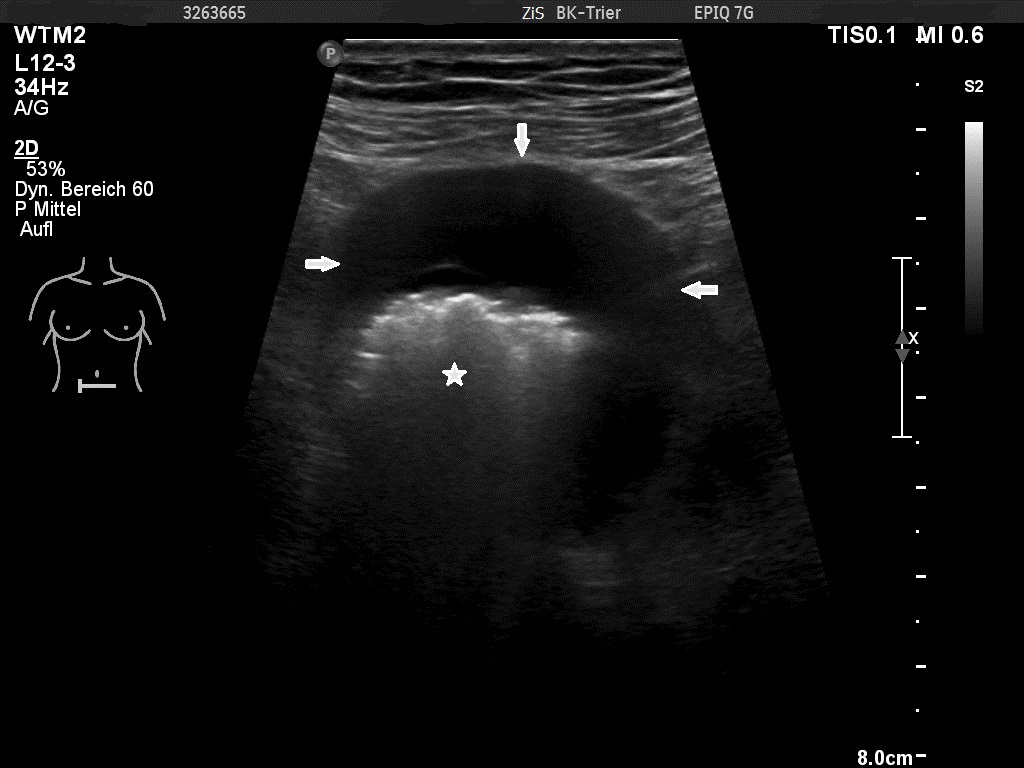

Video 1: Lymphoma in the ileum, transverse scan

The examination revealed a segment of the ileum with substantial semicircular and homogenous hypoechoic wall thickening over a length of about 10 cm. There was no differentiation of wall layers possible. There was also no intraluminal narrowing of the thick- walled bowel segment or bowel dilatation. Colour Doppler revealed straight vessels within the hypoechoic thickened wall.

Ultrasonographic signs of bowel lymphoma are variable. Circumferential wall thickening is the most common pattern on sonography where a common described feature is of a thickened hypoechoic to anechoic wall with an echogenic centre and is described as a the “target-sign” [7,8]

A classic target pattern with no detectable wall layers is characteristic of advanced circumferential intestinal infiltration. Aneurysmal dilatation of the involved bowel may be seen, caused by an infiltration of the muscularis propria and destruction of the autonomic nerve plexus by the tumour. Lymphoma rarely results in bowel obstruction because the tumour does not elicit a desmoplastic response. Lymphoma infiltration sometimes is confined to the mucosa where only transmural involvement forms part of the circumference of the bowel wall [1,7,8].